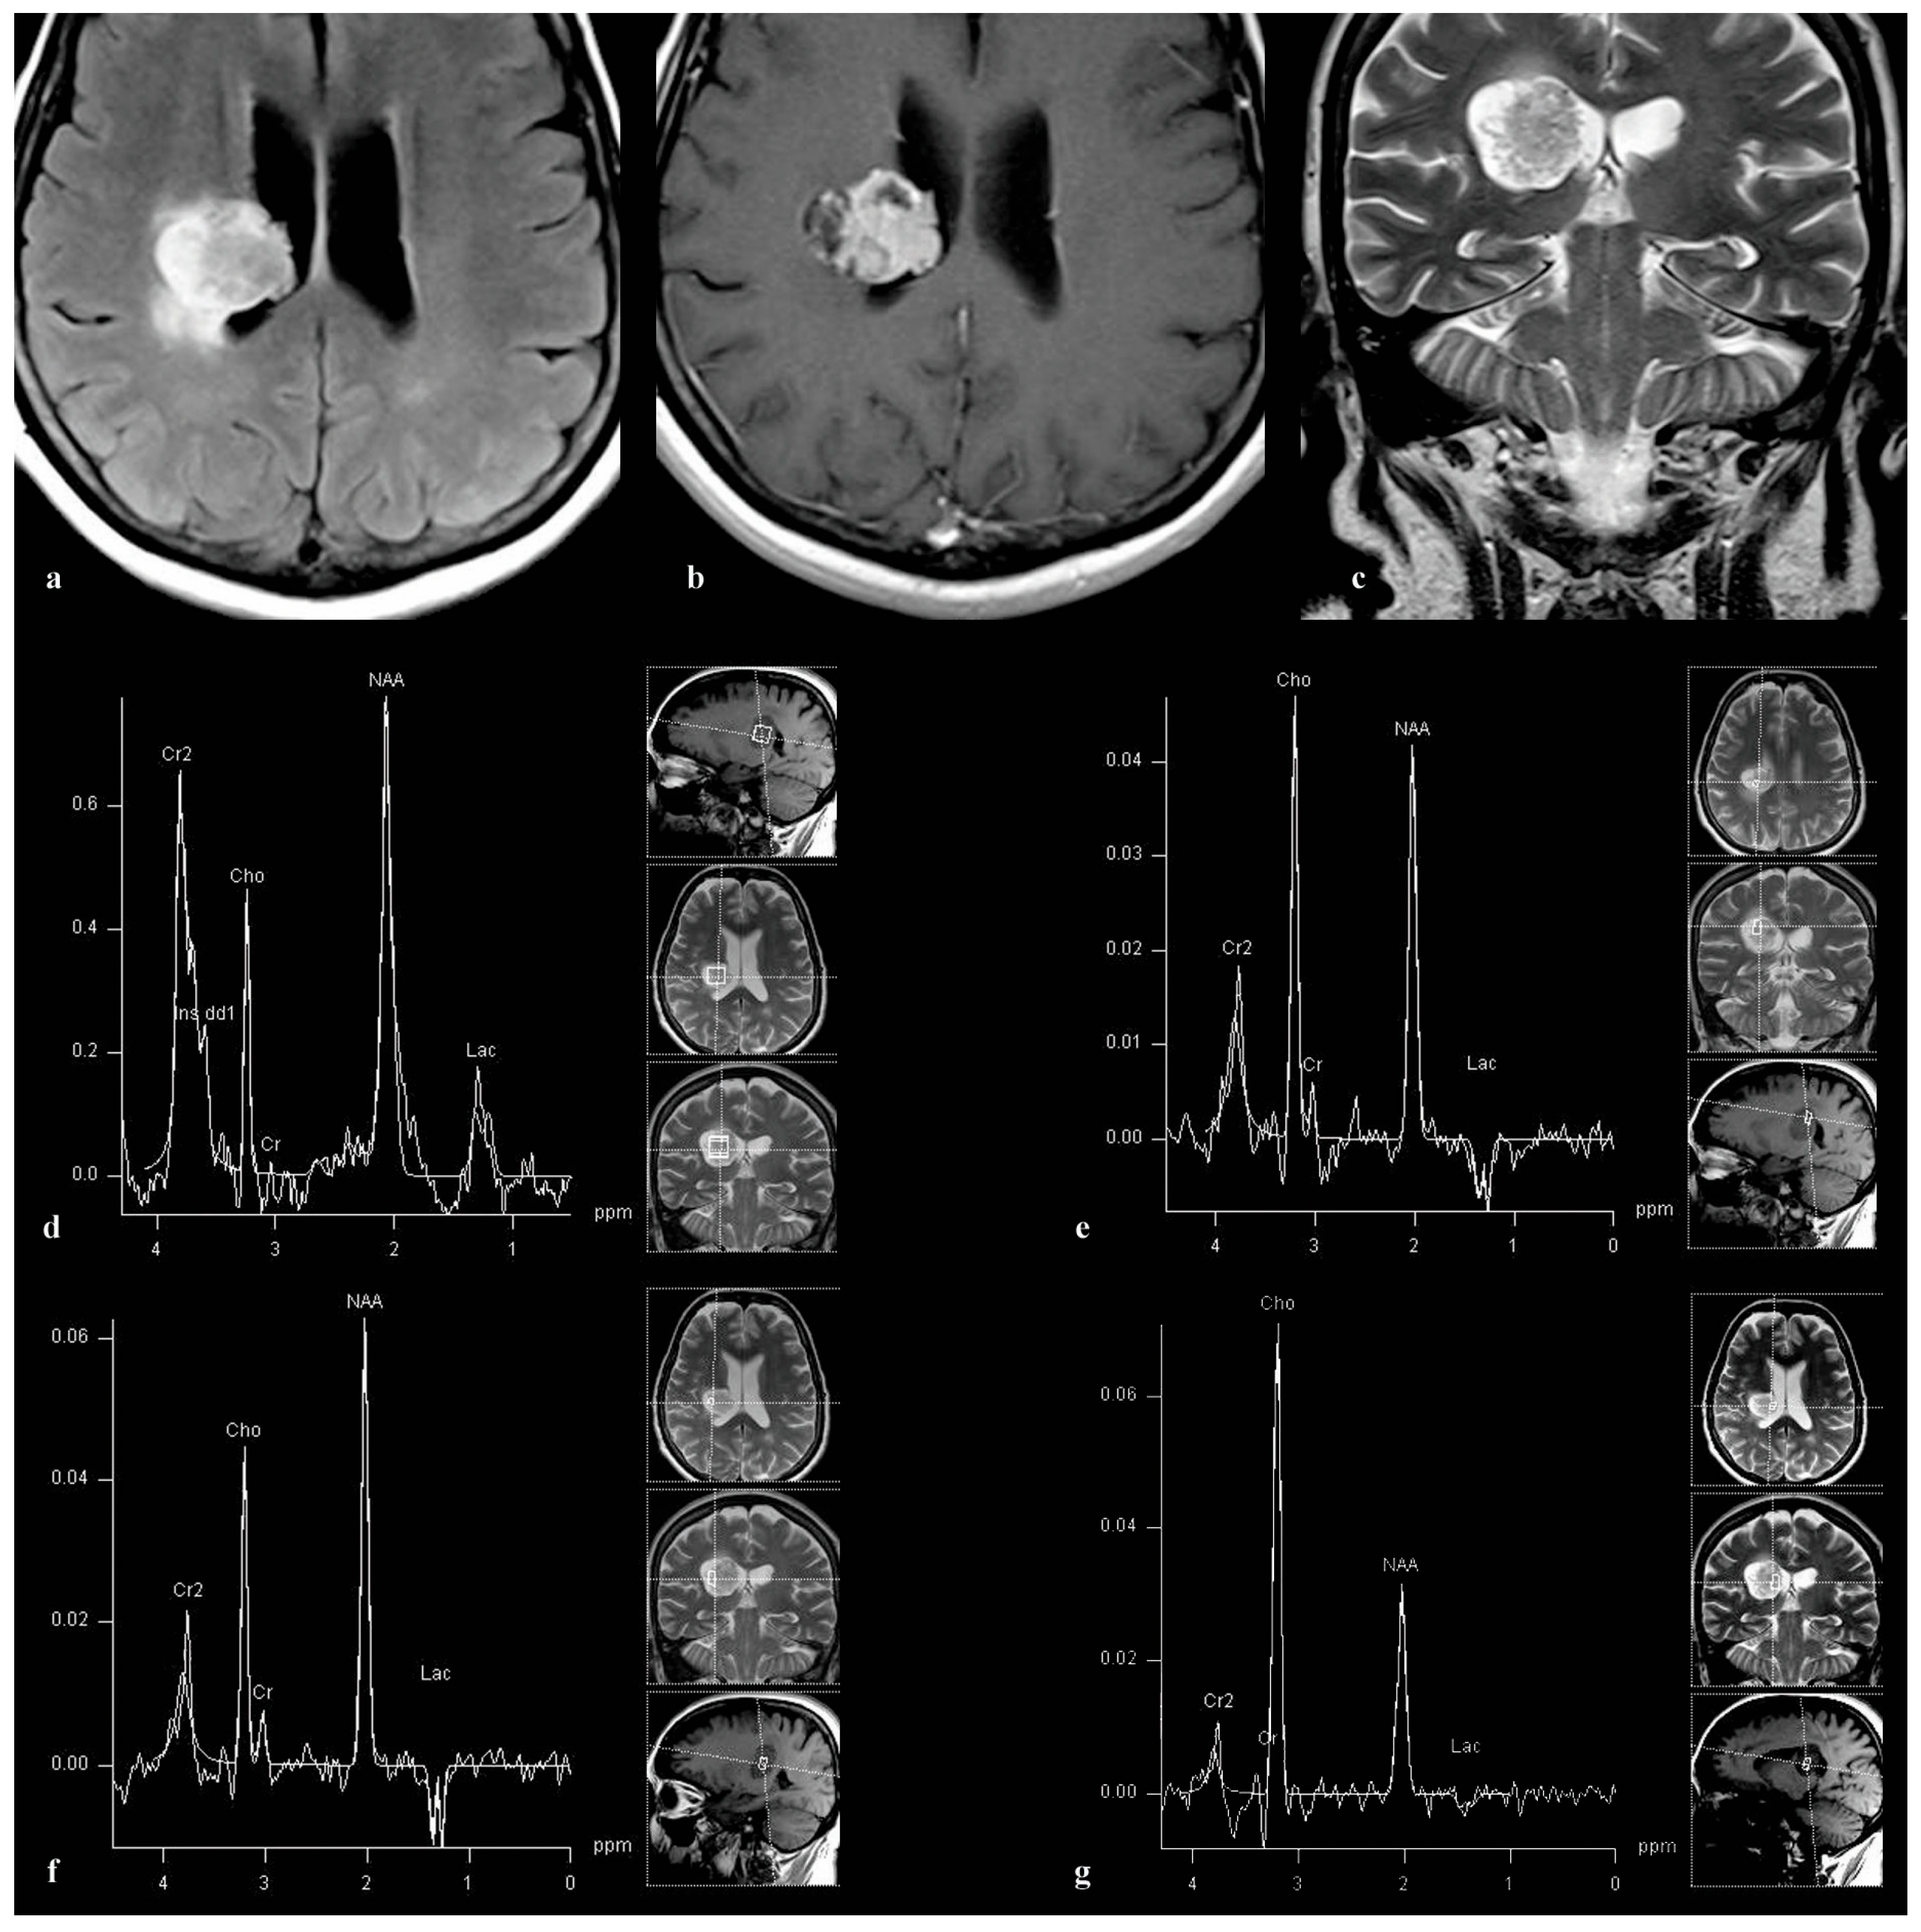

3.3. Patient 3

3.4. Patient 4

3.5. Patient 5